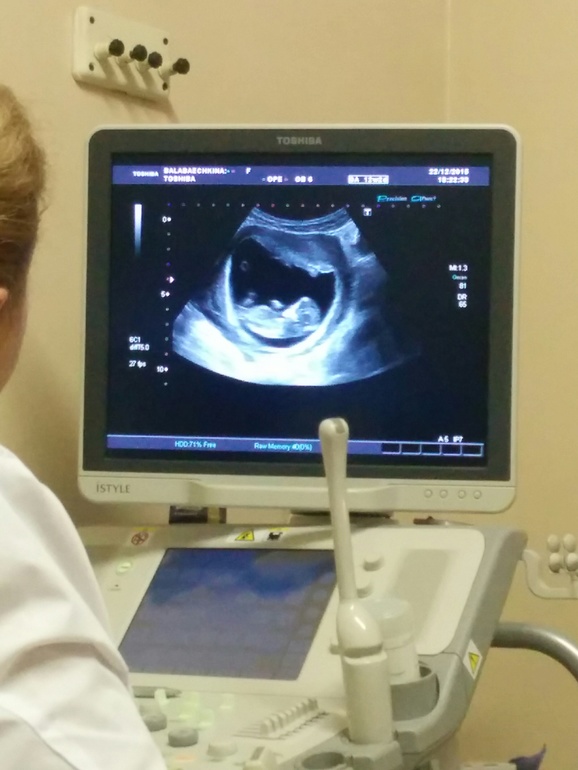

Вчера вечером была на скрининге! Мужу разрешили присутствовать, он всё снимал на телефон! Какое же счастье во мне живёт, растёт и развивается! Ктр 53 мм, всё в норме, сердечко 167 уд/мин. Наш кроха постоянно поднимал ручки к голове, болтал ножками, а узистка сказала, что видела как он подпрыгивает как будто )))

Срок поставили 11 и 5, а по моим подсчетам 11 и 6 было. Значит всё в норме, всё соответствует!

P.S. скриншот с видео не очень чёткий, но для общего понимания прикреплю :)